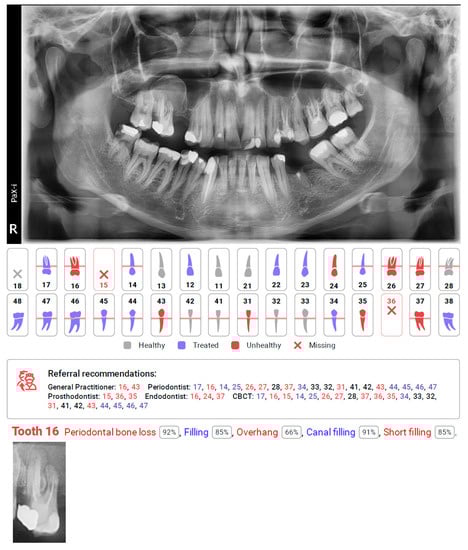

Figure 3.

Diagnocat report, with missing detection of cyst in the right maxillary sinus in the region of tooth 16 and automating caption of tooth with detected other pathologies. Referral recommendations suggest additional CBCT diagnosis for this tooth as well as consultation with an endodontist.